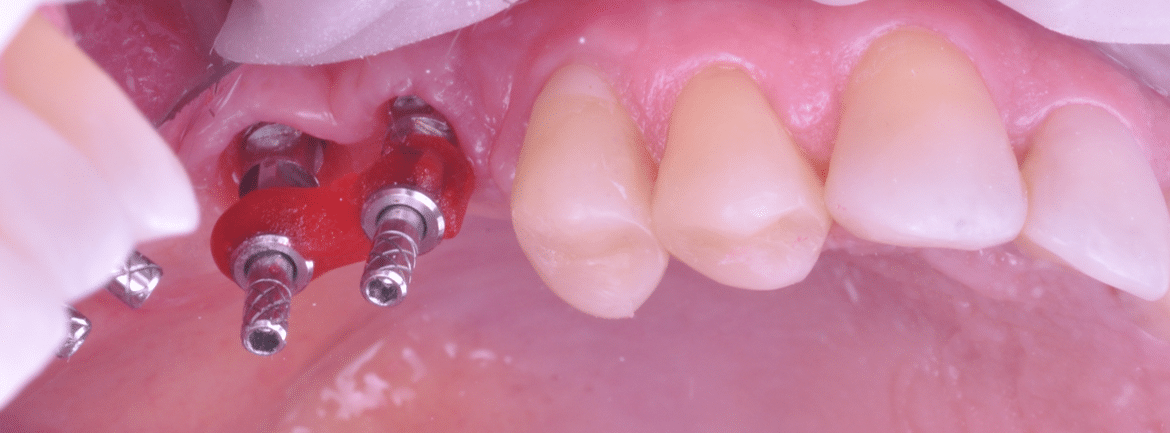

Împreună cu pacientul, am optat pentru inserarea implantelor cu ajutorul ghidului chirurgical pentru a plasa implantul în poziția protetică ideală și pentru a permite realizarea coroanelor insurubate pe implant. A fost efectuată scanarea digitală a arcadelor și a ocluziei pacientului, iar împreună cu tehnicianul radiolog de la DigiRay a fost suprapus fișierul .stl al amprentei digitale peste fișierul .dcm de la CBCT, utilizând software-ul 3Shape.

S-a planificat individual poziția și axul de inserție al fiecărui implant.